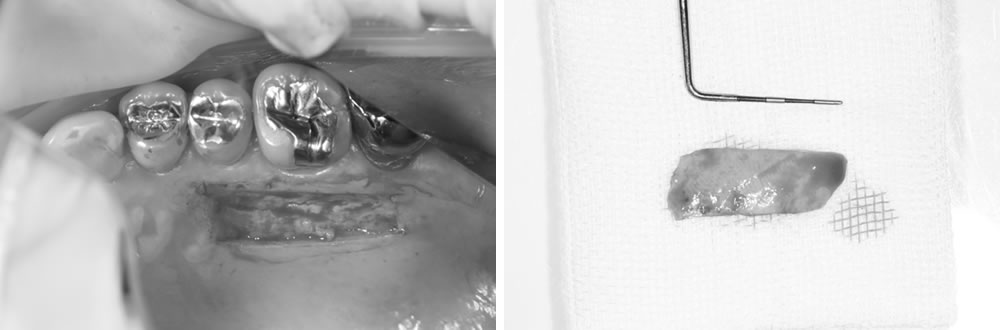

メタルインレーの除去

当該歯のメタルインレーを除去したところ、歯の内部に2次カリエス(虫歯の再発)を認めました。

う蝕検知液(虫歯部分に着色する薬液)を使用しながら、慎重に虫歯除去を行ったところ、遠心に歯根破折を確認しました。歯周ポケットが深かった部位と破折線が一致しており、このままつめ物を装着しても予後不良となる可能性があることを患者さまに説明したところ、抜歯とインプラントによる治療を希望されました。

また、他の銀歯の下にも複数の二次カリエスが認められたため、患者さまは口腔内全体の銀歯を除去し、再治療を行うことを希望されました。